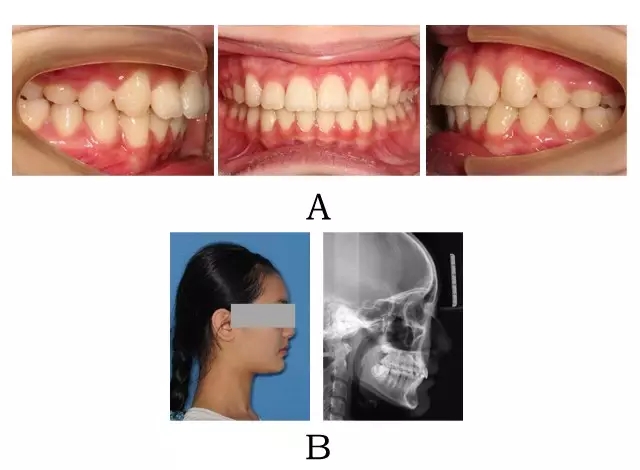

圖 3-3:頜位性突面畸形矯形治療臨床療效及頭顱側位影像變化。

(A) 咬合改善 (B) 側貌改變

Figure 3-3. Treatment outcomes for mandibular positional prognathism. (A) Occlusion correction. (B) Facial esthetic improvement.